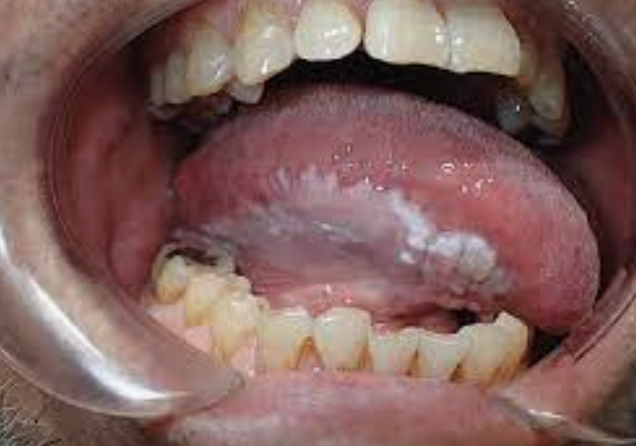

What is the most likely diagnosis?

Describe lesion?

Treatment?